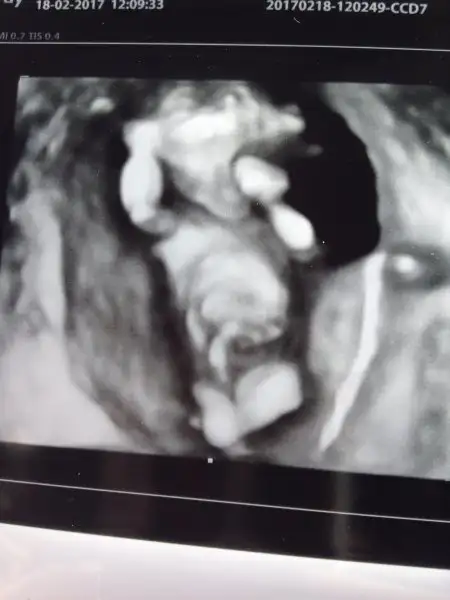

Yaa maşallah çok tatlı tam gözüküyor burda dıktor da çocukta iyiymiş ne güzel resim ya maşallah

Sağol canım, 12+1 ultrason görüntüsüYaa maşallah çok tatlı tam gözüküyor burda dıktor da çocukta iyiymiş ne güzel resim ya maşallah